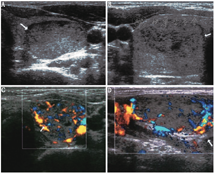

超声检查可以明确甲状腺大小、血供,发现甲状腺结节的位置、大小、数目和特征。大多数GD患者的甲状腺超声表现为弥漫性肿大且呈低回声,这主要是由于甲状腺内血流量增加、细胞密度增加、胶质含量减少及不同程度的淋巴细胞浸润(图1)。彩色多普勒超声中甲状腺血供丰富(与甲亢严重程度相关) (图2),可借此帮助鉴别GD和甲状腺毒症的其他原因,如破坏性甲状腺炎、外源性甲状腺素摄入过多(人为甲状腺毒症),这些改变甲状腺血供一般不增加。彩色多普勒超声也可帮助鉴别1型和2型AIT,后者常表现为血供减少。

TMNG的甲状腺常比弥漫性甲状腺肿的甲状腺大,通常回声不均匀且合并大小不等及回声不均的结节(图3)。这些结节部分具有功能,部分是无功能的。超声引导下细针穿刺活组织检查(简称活检)一般只考虑穿刺无功能结节,因为甲状腺显像表现为热结节者为肿瘤的概率极低[24]。TAs超声通常表现为实性、等或低回声且边界清楚的结节,结节边缘或结节内、结节周围血供丰富(图4)。